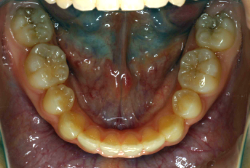

「歯並びの凸凹を直したい」という主訴で来院したケースです。診断の結果、たしかに「叢生」という隙間が足りないと言うことが原因の凸凹症例でした。

しかし、それ以上に問題なのは「前歯の噛み合い方が深すぎる」という症状で、初診の歯の正面写真を見ると下の前歯が全く見えません。こういう症状を矯正学では「過蓋咬合(かがいこうごう)」と言います。過蓋咬合を放置すると、将来的に顎関節に悪影響を与えるとされており、顎関節症の原因因子の一つです。また下の前歯の先端が、上の前歯の裏側の歯茎と強く接触するため、歯周病の原因にもなります。

検査の結果、凸凹が軽症なため非抜歯で矯正すること可能と判断、マルチブラケット装置にて治療しました。治療後は歯並びが綺麗になっただけでなく、噛み合わせ的にも正しい状態が確立しています。